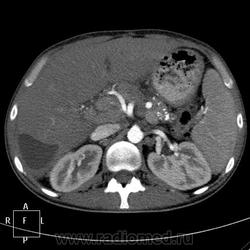

КТ (часть кадров выложу позже ). Цель направления на КТ - образование правой доли печени, исключить образование тела п.ж.

). Цель направления на КТ - образование правой доли печени, исключить образование тела п.ж.

артериальная:

Панкреатическая:

Портальная:

В данном случае ранняя артериальная получилась с брачком - контрастировалась нижняя полая (25 сек задержка, триггера нет), панкреатическая 45 сек (стандарт), портальная 70 сек. Отсроченная в печени делается на подозрение на холангиокарциному и гемангиому. Тут почки и не интересовали.

Гемангиома, являясь сосудистой опухолью, будет такого же цвета, как и сосуды, во все фазы. Это - кистовидное образование, стенки относительно равномерной толщины, копящие контраст тонкой полоской. Содержимое образования жидкостной плотности и контраст не копит.

Гепатоспленогмегалия. Начальная портальная гипертензия, холедох не расширен. В воротах печени бугристая масса.... чего? Кальцинаты поджелудочной железы, мелкий камушек в желчном. Вопрос в том, что за кистовидное образование, что за полоса-серп вокруг желчного пузыря, что в воротах печени. Опухоли п.ж. я не нашла.

Данному пациенту в заключении я выставила подпеченочный абсцесс, гепатоспленомегалию, портальную гипертензию, конгломерат лимфоузлов ворот печени, лимфаденопатию желудочной группы л/у, хр.калькулезный панкреатит, ЖКБ с перихолециститом.

В воротах, похоже л/у, а жидкостное абсцесс печени.

Абсцесс печени.